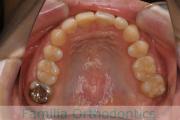

No.22V-409

- 叢生

- 年齢:

- 16歳

- 性別:

- 女性

- 抜歯部位

- 上:

- 44

- 下:

- 8|58

- 主な使用装置:

- FEA

- 治療にかかった費用:

- 86万円

八重歯を治したいということで来院されました。下あごの左ずれのある上顎前突(出っ歯)・叢生(でこぼこ)でしたので、上は左右から、下はで左のみ小臼歯を抜歯して、歯科矯正用アンカースクリューとマルチブラケット法にて治療を行いました。2年強、30回程度の通院が必要でした。

上下とも前歯の叢生(でこぼこ、凹凸、ガタガタ)があるため、保定を怠ると後戻りのリスクがあります。

- ≫治療後

-

上顎

下顎